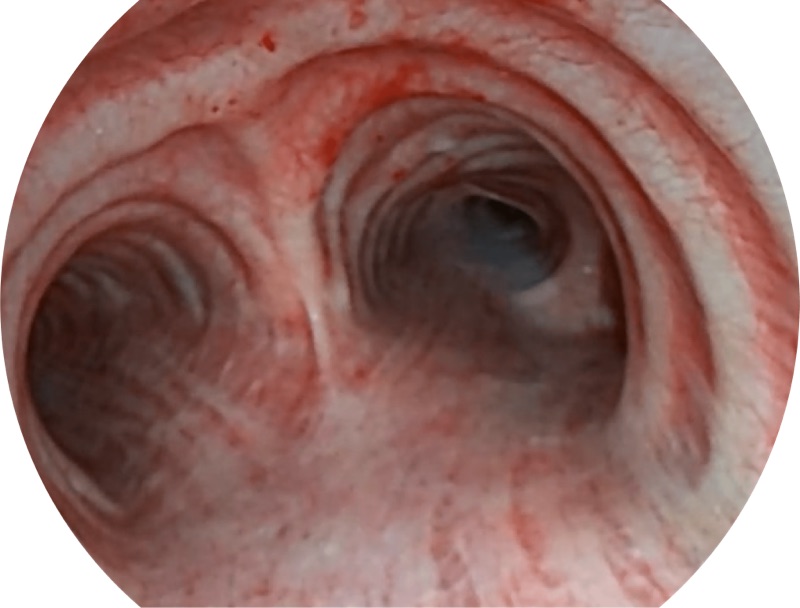

VIST